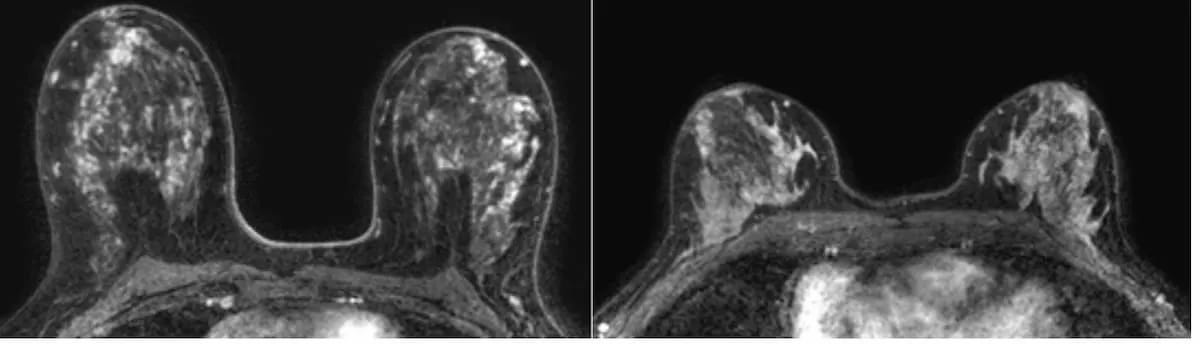

At an amplitude of 200 mT/m and a slew rate of 200 T/m/s, the gradients for the FDA-cleared MAGNETOM Cima.X are reportedly the strongest for currently available whole-body MRI scanners.